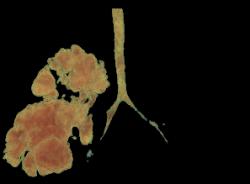

radiotrasparenza, attribuibile a un elemento dell'incubatore. Per una miglior definizione del problema, anche in vista dell'intervento, viene effettuata una TC-polmonare che evidenzia a destra una formazione irregolarmente ovalare di circa 5 cm di diametro massimo, apparentemente ben marginata, con numerose formazioni cistiche aerate circostanti (Figure 2 e Figura 3). Alla luce della diagnosi il bambino viene quindi sottoposto con successo ad intervento di lobectomia parziale dei lobi medio e superiore di destra. |

| Figure

2 a b. TC-polmonare: evidente a dx una formazione

irregolarmente ovalare di circa 5 cm di diametro massimo. | ||

| La

formazione � apparentemente ben marginata, con numerose

formazioni cistiche aerate circostanti. Il successivo decorso postoperatorio non ha presentato complicazioni (2 giorni di ventilazione meccanica e drenaggio pleurico). L'alimentazione gi� avviata con suzione autonoma prima dell'intervento, � stata ripresa il giorno successivo all'operazione con buona tolleranza ed il bambino � stato dimesso, a diciotto giorni di vita, in buone condizioni generali ed in allattamento materno esclusivo, con un programma di follow-up presso la chirurgia del nostro istituto. |

Dall'esame |

Figura 3. Ricostruzione TC: l'albero bronchiale con la lesione adenoido-cistica, evidenziata dopo sottrazione del parenchima polmonare circostante.